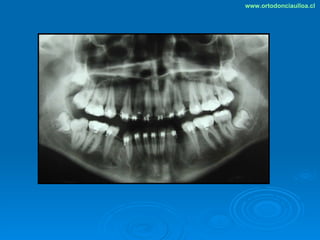

Este documento presenta dos casos clínicos de pacientes que recibieron tratamiento de ortodoncia. El primer caso fue de una paciente femenina de 14 años con apiñamiento dental y mordida cruzada que fue tratada mediante extracción de premolares y alineamiento dental. El segundo caso fue de un paciente masculino de 14 años con clase II esqueletal y desarmonía dentomaxilar que fue tratado con extracción de premolares y corrección de mordida. Ambos casos mostraron mejoría después de 3 años de tratamiento.